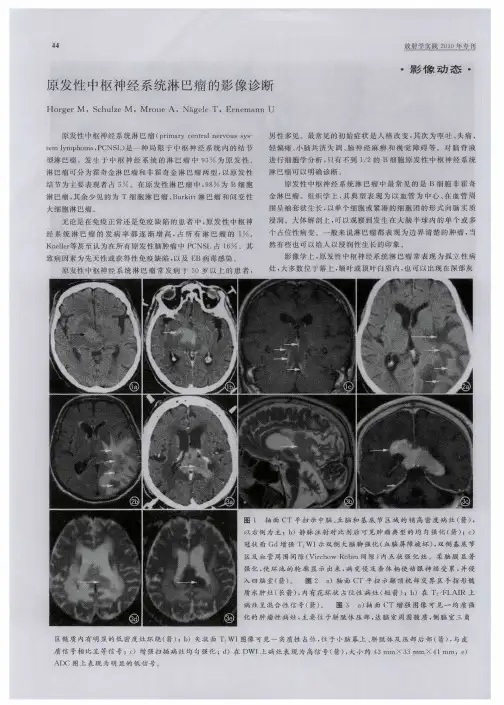

2结果8例为单发,1例多发,其中额顶叶6例,颞叶2例,右小脑1例,胼胝体1例。

病灶呈类圆形为主,少数呈不规则形。

M R 表现与脑灰质相比,多数病灶T1W I 为略低信号(7例),少数为等信号(2例),T2W I 多为等、略高信号(8例),少数为略低信号(1例)。

病灶边缘较清晰,均有占位效应,灶周水肿相对较轻。

注射G d-D TPA 后,8例病灶明显团块状强化,1例中央可见坏死无强化区,周边部呈不均匀强化。